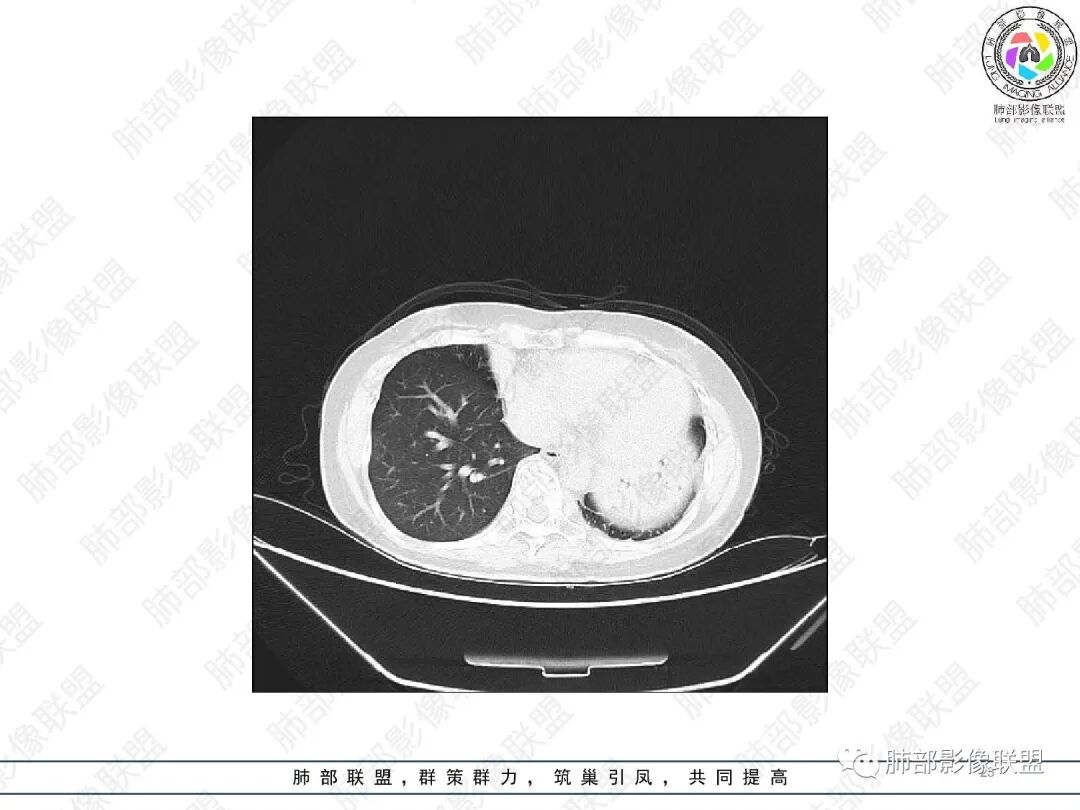

1.中年女性,主因“咳嗽、咳痰半年余”入院,既往史:8年前因左肺病在外院变行左肺叶切除术,诉术后抗结核治疗1年,具体病理等不详。实验室IGE显著增高。

2.胸部CT:右肺上叶及中叶不规则块状影,沿支气管走行方向指套样影,支气阻塞湖嵌塞,腔内可见高密度影。灶周可见磨玻璃,外围见结节影及树芽征。左肺体积缩小,见不规则条索影、胸膜增厚,纵隔牵拉左移。

3.综合分析:结合患者病史及胸部CT主要鉴别ABPA(右肺上叶不规则块影,指套样顺延支气管方向,抗结核治疗1年,肺部病灶仍明显)及继发性肺结核TB(右肺上叶不规则肿块,其可见高密影,边缘模糊,周围卫星灶、树芽征,沿支气管爬行)。

完善气管镜及病理、检验结果(IgE显著增高)等支持ABPA诊断。且给予激素及伊曲康唑治疗后复查胸部CT提示病灶较前吸收,所以诊断明确。